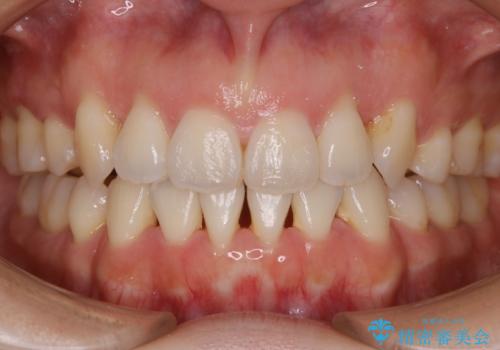

前歯のオープンバイト インビザラインで咬み合わせを改善